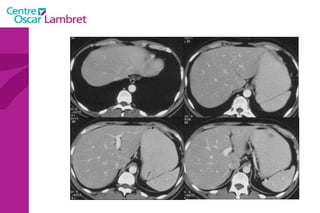

Tube Digestif L’Estomac

Tube Digestif L’estomac : Situation dans l’hypocondre gauche et l’épigastre. taille variable (selon  patient et  degré de remplissage) 3 moyens d’attache. Paroi fine et régulière  < 10 mm ( fiable si estomac distendu) grande courbure = sous phrénique G pylore,le Cardia et la petite courbure.

L’estomac Il est très vascularisé par des branches qui proviennent du tronc cœliaque issu de l’aorte.

Différentes parties de l’estomac cardia Petite courbure Grande   courbure pylore antre fundus Antre pylorique duodénum Poche à air   gastrique corps